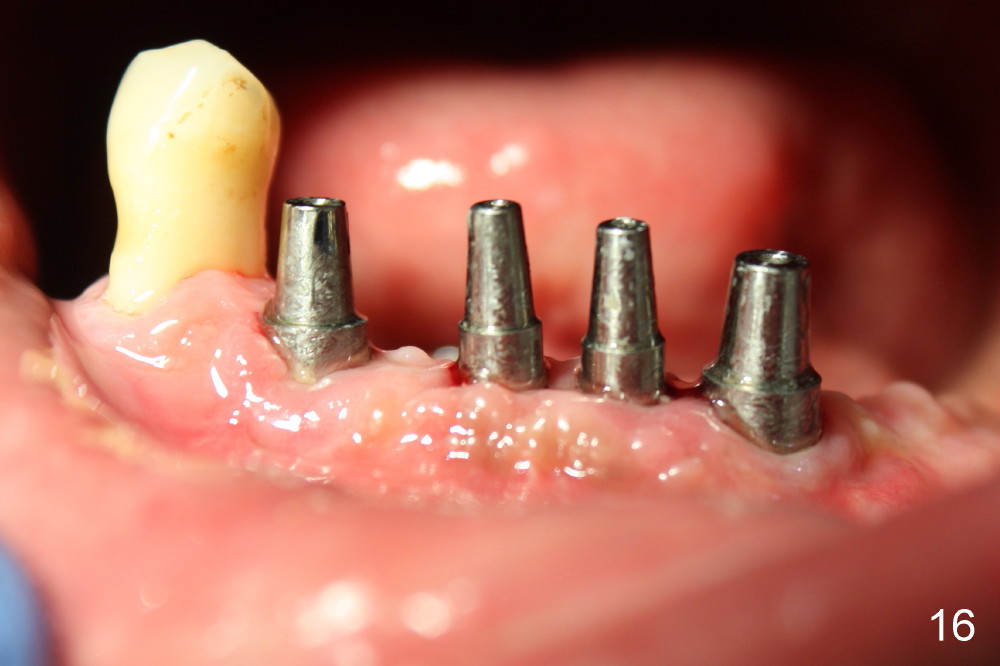

The 4 anterior implants appear to have been osteointegrated 5 months postop (Fig.14,15). More gingiva has covered the top portion of the implants (Fig.16). Ball abutments are placed for an overdenture (Fig.17).